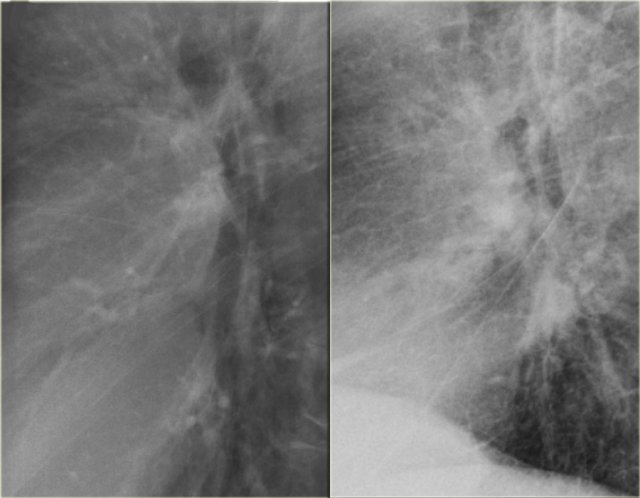

On the left a patient with congestive heart failure.

There is an increase in the caliber of the pulmonary vessels and they have lost their definition because they are surrounded by edema.

On the left another patient with congestive heart failure.

The lateral view nicely demonstrates the increased diameter of the pulmonary vessels and the hazy contours.

Notice also the septal lines and the accentuated interstitium.

Furthermore the fissura major is markedly thickened.